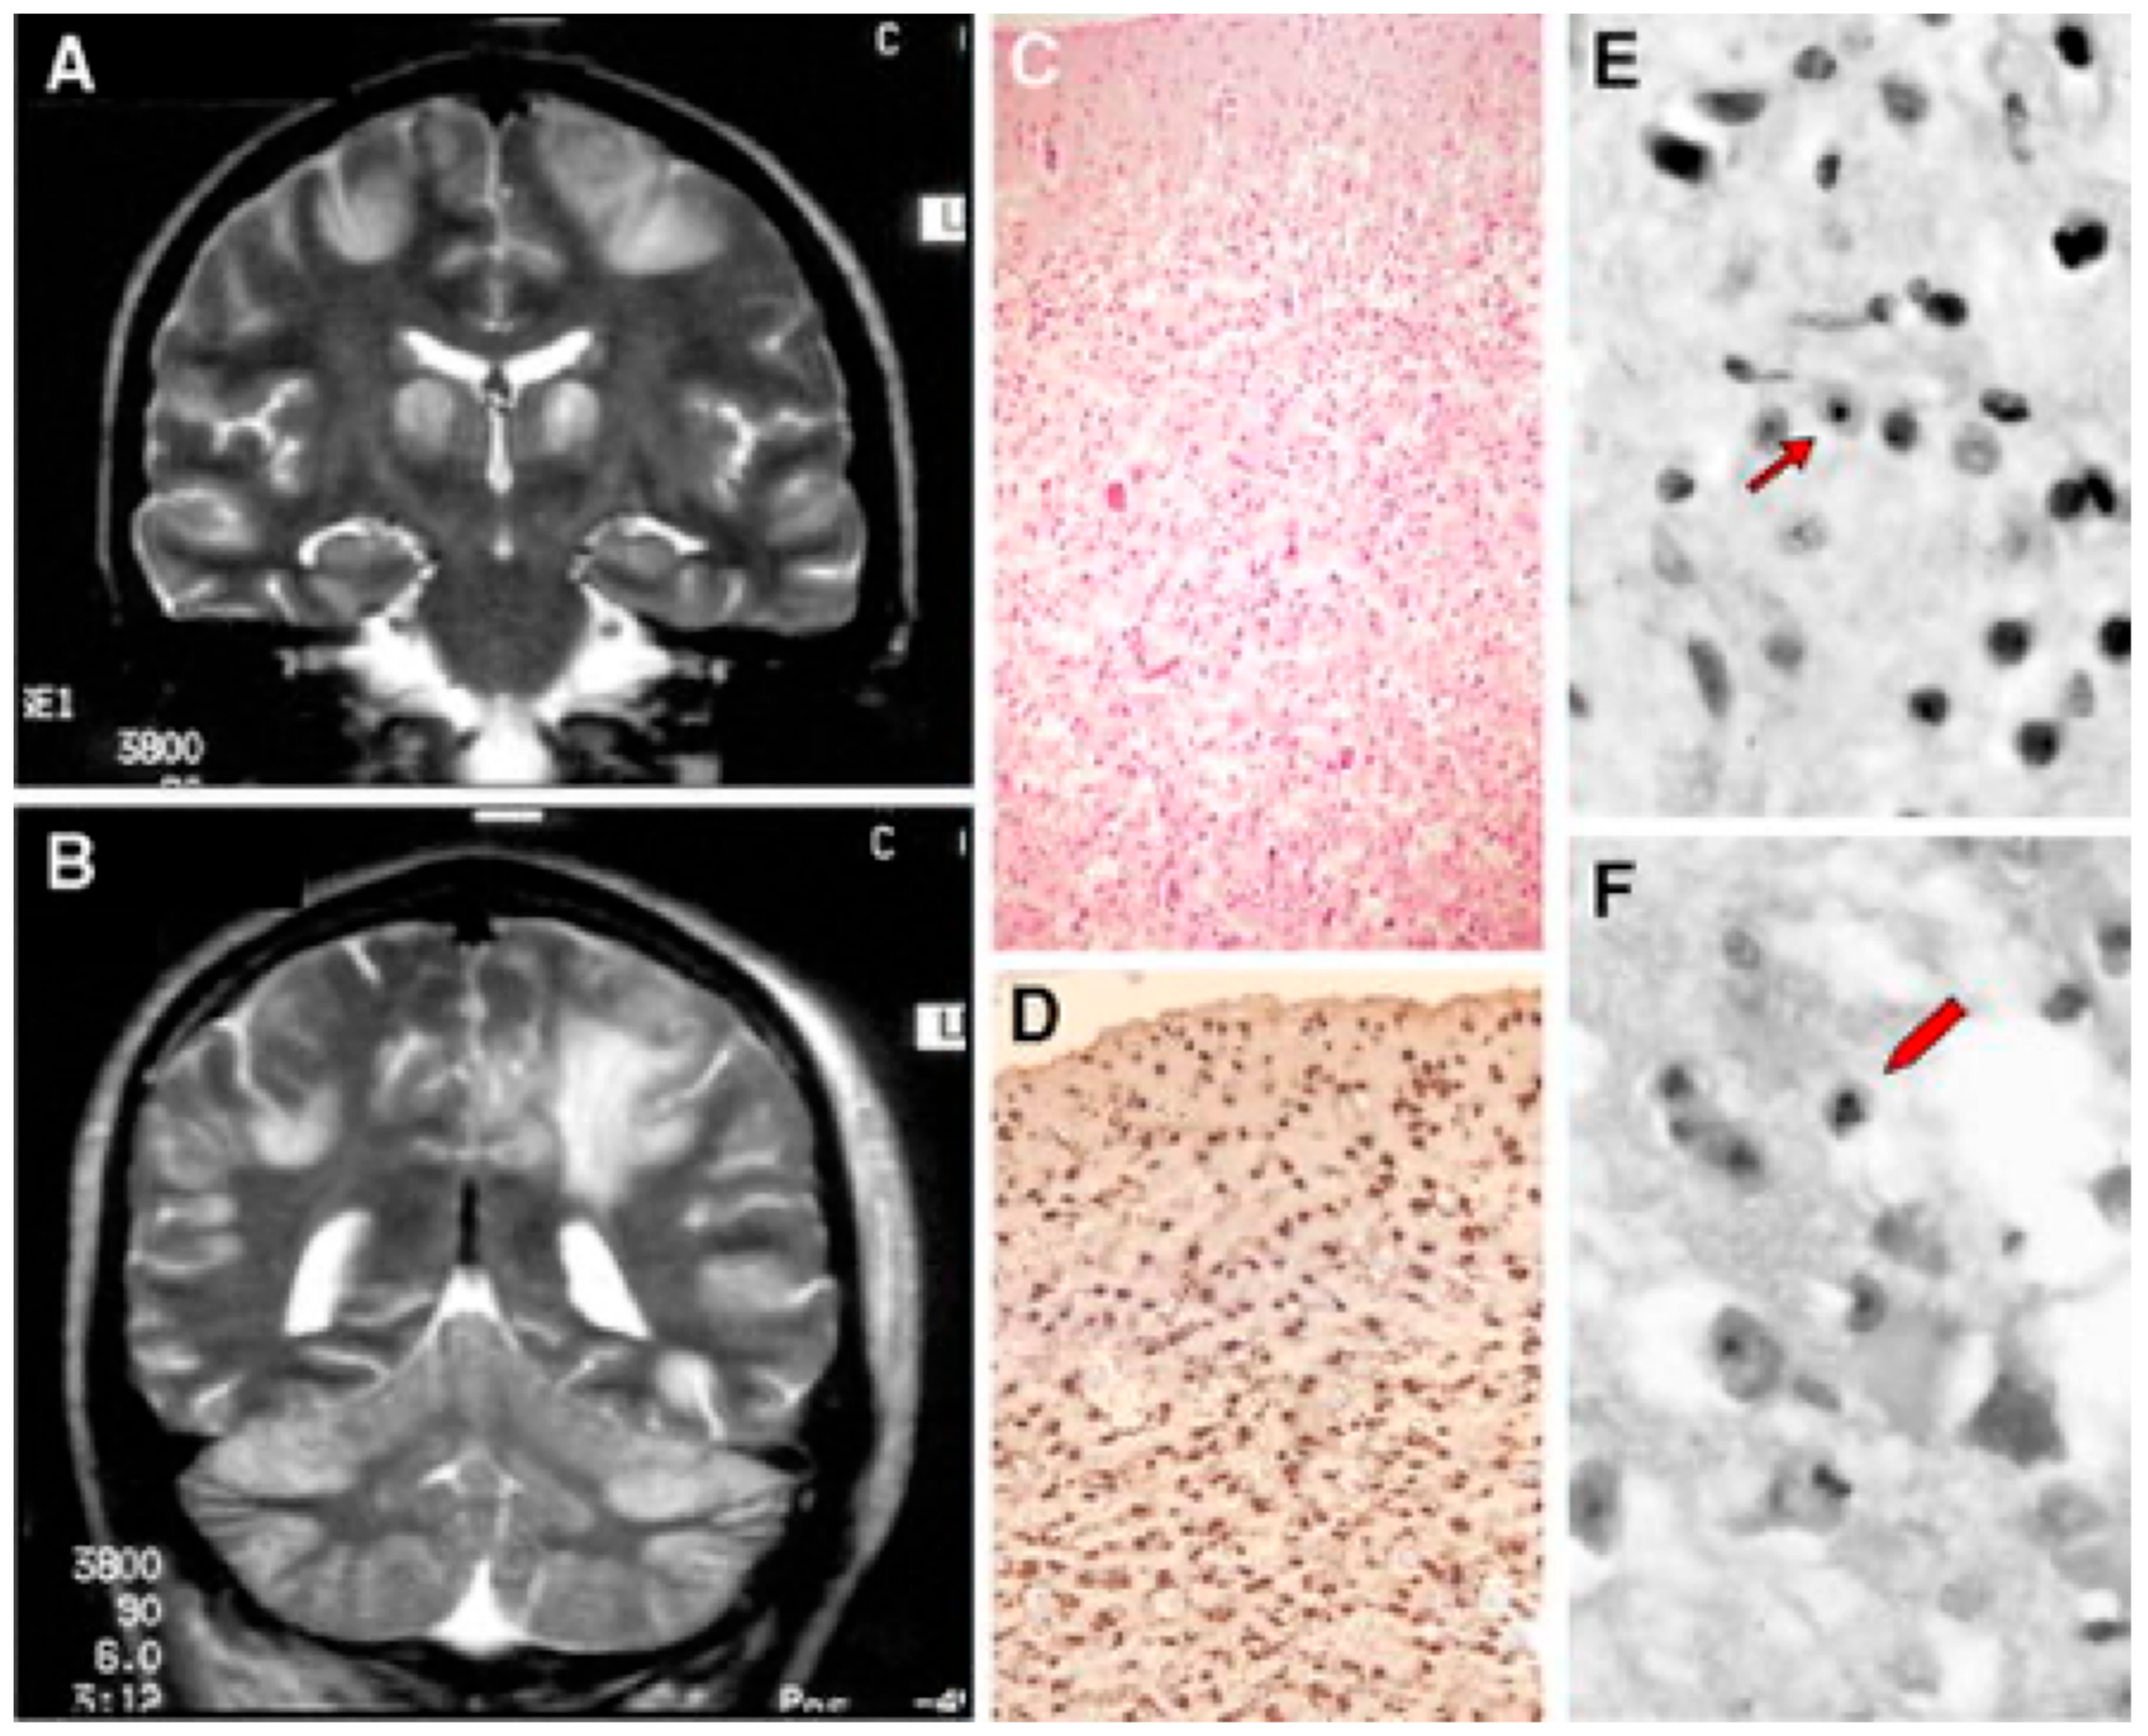

- Simonati, A.; Filosto, M.; Savio, C.; Tomelleri, G.; Tonin, P.; Dalla Bernardina, B.; Rizzuto, N. Features of Cell Death in Brain and Liver, the Target Tissues of Progressive Neuronal Degeneration of Childhood with Liver Disease (Alpers-Huttenlocher Disease). Acta Neuropathol. 2003, 106, 57–65. [Google Scholar] [CrossRef] [PubMed]

- Filosto, M.; Tomelleri, G.; Tonin, P.; Scarpelli, M.; Vattemi, G.; Rizzuto, N.; Padovani, A.; Simonati, A. Neuropathology of Mitochondrial Diseases. Biosci. Rep. 2007, 27, 23–30. [Google Scholar] [CrossRef]

- Ferrari, G. Infantile Hepatocerebral Syndromes Associated with Mutations in the Mitochondrial DNA Polymerase-gammaA. Brain 2005, 128, 723–731. [Google Scholar] [CrossRef]